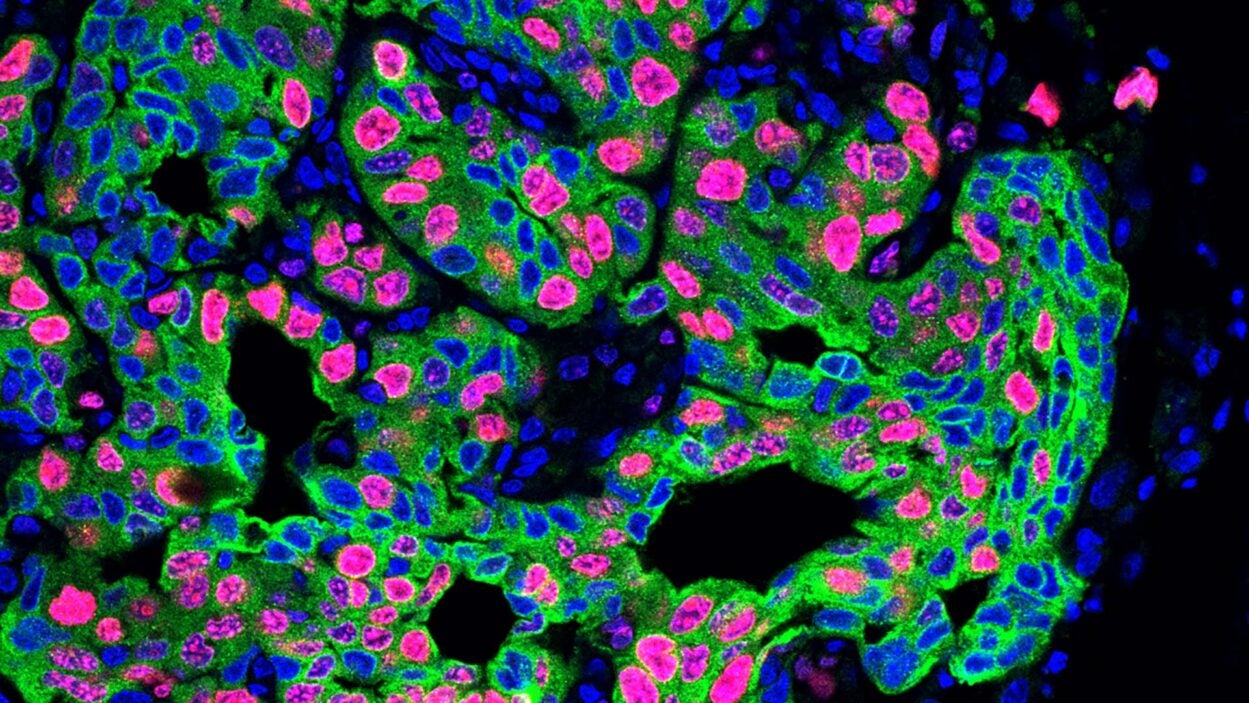

Research from new CSHL Assistant Professor Katherine Alexander suggests that nuclear speckles could influence kidney cancer patient outcomes. Read the story »

Her team will explore mysterious cellular structures known as nuclear speckles and their role in diseases such as cancer. Read the story »

Feature

An angry peacock is no joke. Like the colorful bird and its tall tail feathers, cancer biology can make for some eye-catching images. Read the story »